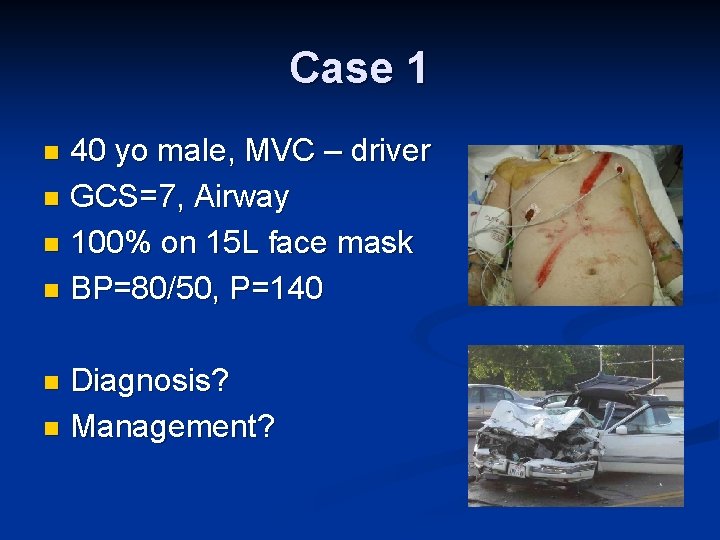

Case 1 40 yo male, MVC – driver n GCS=7, Airway n 100% on 15 L face mask n BP=80/50, P=140 n Diagnosis? n Management? n

Decision Making Airway n Breathing n Circulation n SHOCK Hemodynamically Stable Transient Responder How are you going to assess? Hemodynamically Unstable

Shock Scalp n Chest – clinically vs. chest x-ray n Abdomen n FAST n DPL n Pelvic X-ray n Extremities – Femur n Other causes of shock – cardiogenic, obstructive, anaphylactic, septic n

Case 1: Learning Points Recognize Shock n Hemodynamically unstable = OR n Role of FAST, DPL n Permissive hypotension in resuscitation until bleeding controlled n